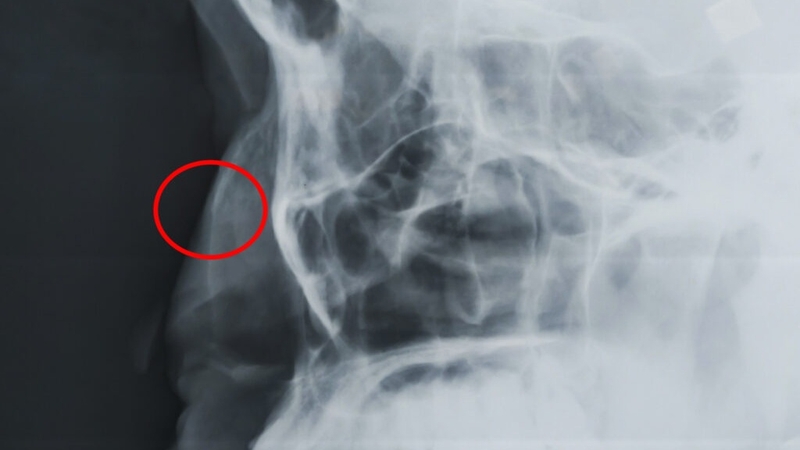

Bác sĩ sẽ quan sát mũi bị gãy và khu vực xung quanh để xác định những biến dạng do chấn thương. Trong một số trường hợp, bệnh nhân sẽ được chụp X-quang hoặc CT để đánh giá mức độ nghiêm trọng.

Gãy xương mũi được phân loại thành các dạng khác nhau, bao gồm: Gãy di lệch sang bên (xương hoặc vách ngăn), gãy không di lệch, gãy hỗn hợp và gãy nén. Mỗi loại gãy đều có những đặc điểm và triệu chứng riêng, đòi hỏi cách điều trị thích hợp.